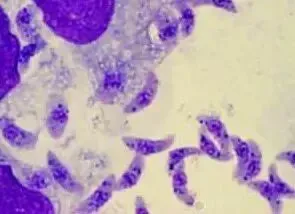

弓形虫,被科学家们称做「地球上最成功的寄生虫」之一,因为它们无处不在、遍布全球。夏秋季处于高传染期,可感染包括人在内的一百四十多种动物,能够引起人兽共患的弓形虫病。

我们先了解下,弓形虫是怎么传播的。猫是弓形虫的主要传染源,弓形虫在猫科动物体内进行繁殖,产生大量未孢子化的卵囊,并随着粪便排出,一段时间后会孵化为孢子化的卵囊,污染中间宿主(人、猫、狗、猪、牛、羊、鸡等)。